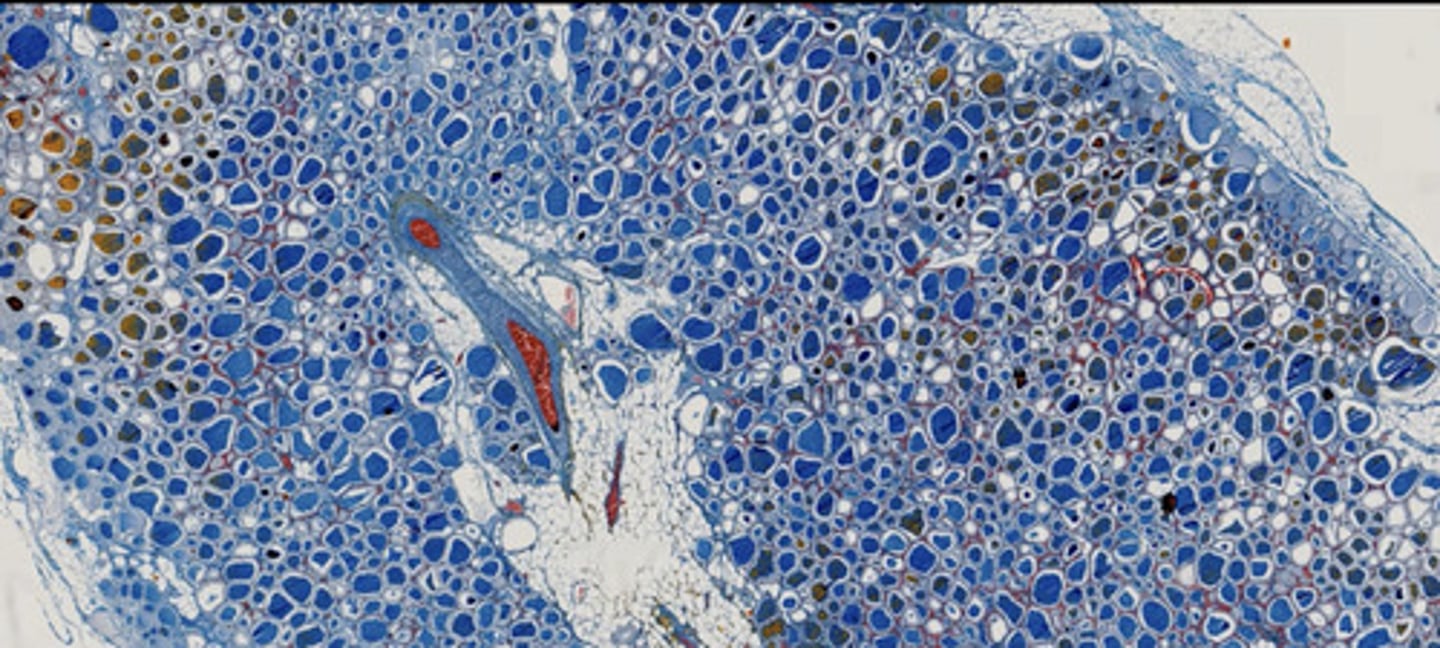

Nerka nastrzyknięta - obrazowanie naczyń (masa iniekcyjna z błękitem metylu)